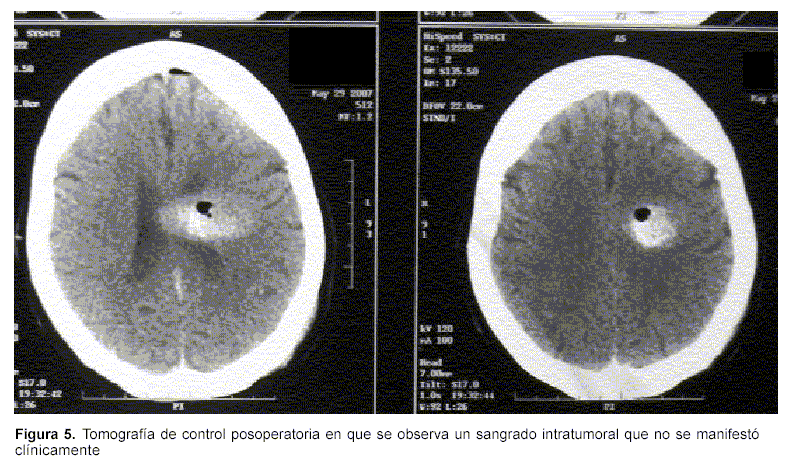

Complicaciones: en un caso se observó en la tomografía de control posoperatoria hemorragia intratumoral, que no se manifestó clínicamente (figura 5).

En la presente serie, sólo en un caso se constató una hemorragia intratumoral en la tomografía de control posoperatoria que no generó síntomas. Este hallazgo puede producirse hasta en 7% de los casos(21). En esta serie corresponde a 5%.